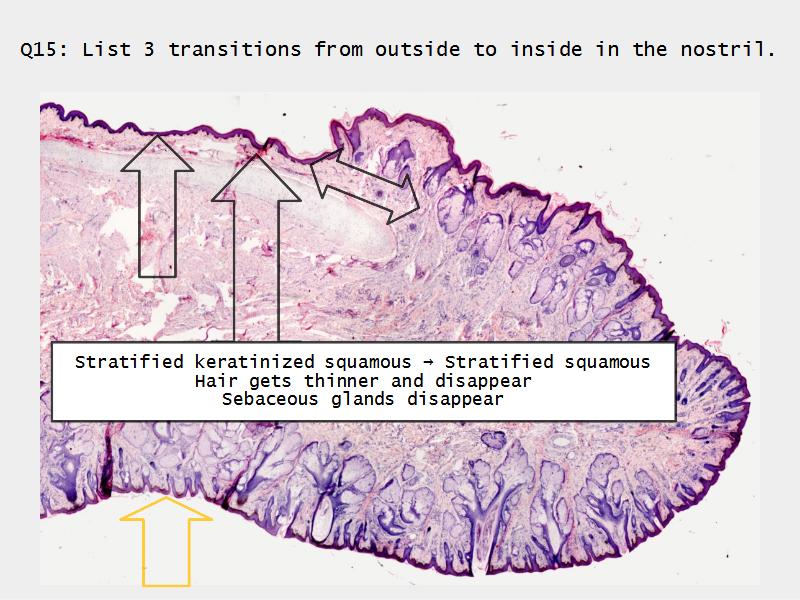

Transitions

- Slide 71: Nostril

Nostril